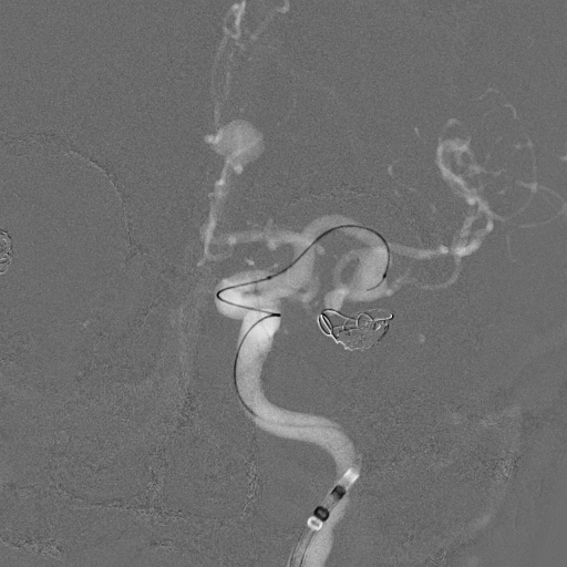

• The patient presented with multiple unruptured giant wide-neck aneurysms. A pre-treatment panangiography revealed a right posterior communicating artery aneurysm measuring approximately 8x8mm and an additional 8x6mm saccular aneurysm in the left azygos pericallosal artery—an exceedingly rare anatomical variation.

• The left middle cerebral artery aneurysm (9x5mm) had previously been treated with a coil but required further intervention.

• Under general anesthesia, a puncture was performed on the right femoral artery, and a CEREBASE 8F introducer catheter was inserted.

• The left internal carotid artery (ICA) was accessed and a pathway was built using TJWY’s FREPASS microcatheter.

• A 5x20mm NUVA flow diverter, designed by TJWY, was deployed to treat the aneurysm in the posterior communicating artery with precision, achieving immediate blood flow stagnation.

• The neck of another aneurysm in the pericallosal artery was protected with a 10mm PCONUS intrasaccular device, and successfully embolized with 3 coils.